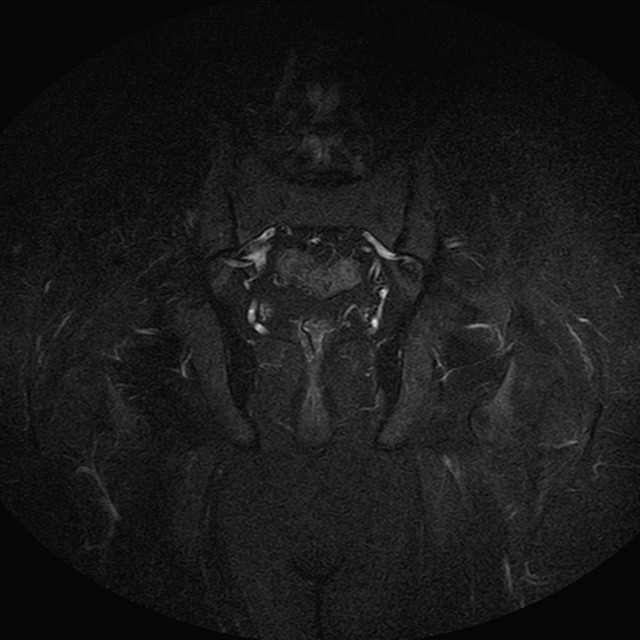

Esami: RMN BACINO

eSTIR

Evidenti e simmetriche alterazioni osteofitosiche in regione coxo femorale con riduzione delle rime articolari. Degenerazione completa del cercine glenoideo. Non attuali segni di versamento articolare. Non segni di edema osseo che escludono attuale algodistrofia od osteonecrosi. Lieve e simmetrica riduzione del trofismo della muscolatura glutea.